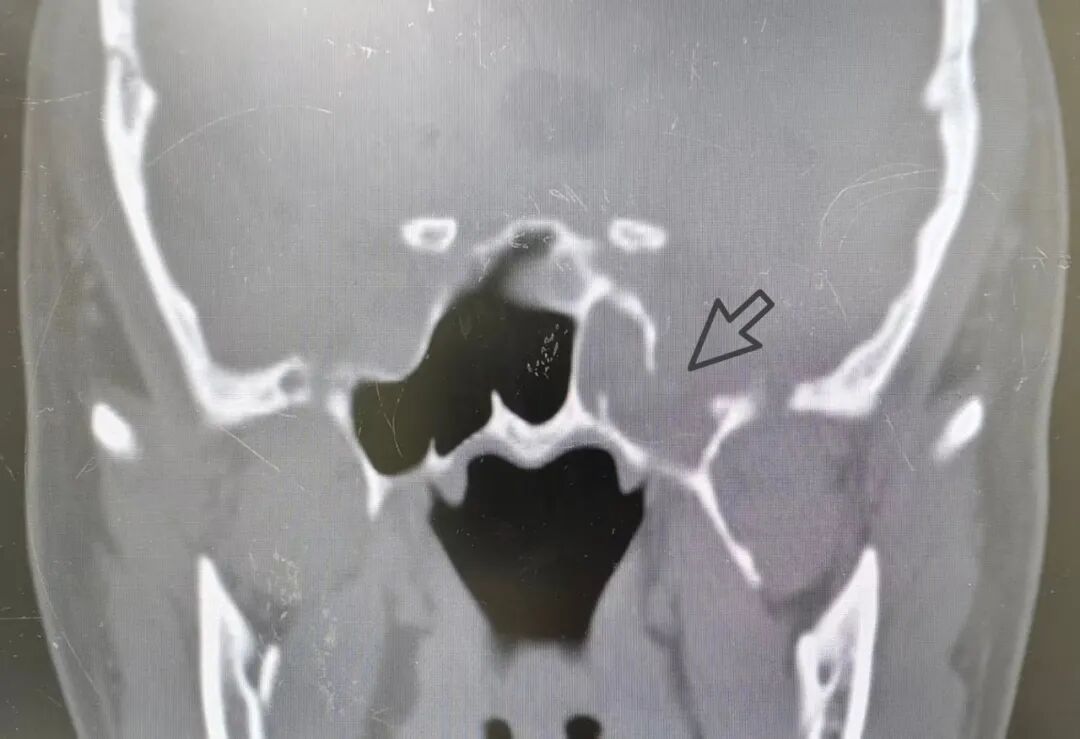

很多朋友的认知中,“流鼻涕”这个症状太常见了,多半不是感冒就是鼻炎。42岁的周先生也不例外,左侧鼻涕哒哒一个多月了,到社区医院开了感冒药和鼻炎药,非但没有缓解,近来还出现了头晕的不适。于是再到我们医院门诊就诊,“邓主任啊,我这也没有发烧,也没有鼻子塞,奇怪了,低下头清鼻涕流的还要厉害,而且还是一侧”。 邓主任建议周先生先做个电子鼻咽镜检查,内镜发现他鼻黏膜、鼻甲并没有明显的充血肿胀,鼻道也较为通畅。嘱其低头和按压左侧颈外静脉处时,意外发现中鼻道后上方清水样流出。 于是收集周先生的左侧鼻腔流出液体进行葡萄糖定量分析3.7mmol/L,并且检出了β2-转铁蛋白阳性。这时邓主任心中已有了方向,继续询问周先生既往有没有头部外伤过,有没有做过手术,结果都是否认的。接下来有必要完善的检查就是鼻窦CT了,果然发现左侧蝶窦外侧壁骨质缺损伴窦腔内低密度影。原来周先生鼻腔流出的清水不是鼻涕,而是脑脊液!周先生得的是自发性脑脊液鼻漏! 图:箭头所示为左侧蝶窦骨质缺损处